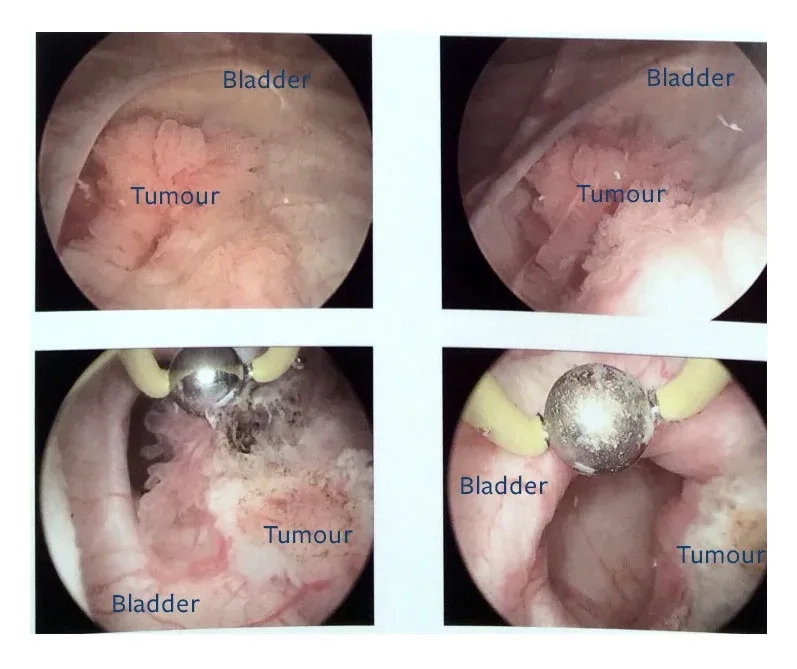

Exploring options for bladder cancer treatment